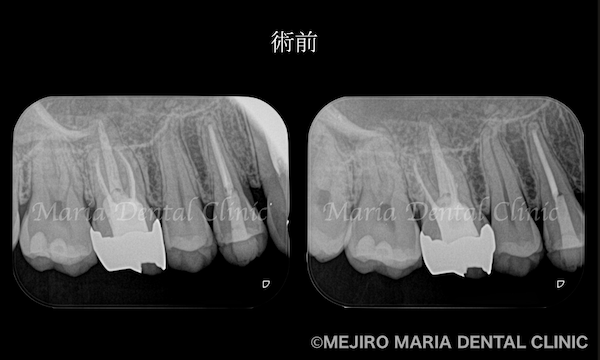

患者様は1年前に、右上4番の歯に違和感を覚え、近隣の歯科医院にて初めての根管治療(抜髄処置)を行うも、症状が改善されませんでした。その後、他の歯科医院に相談するも、症状の原因となる歯の特定には至ることができず、目白マリア歯科を受診されました。

患者様ご自身は、1年前に根管治療を行った右上4番の歯の予後不良を疑っていました。しかし当院の診査にて、患者様の訴える症状の原因は、数年前に根管治療を行った右上6番の歯の予後不良による根尖性歯周炎と診断しました。

治療のコンセプトに沿って精密根管治療を2回で終了させ、暫間冠(仮歯)にて3ヶ月間の経過観察を行いました。3ヶ月後には症状は完全に消失、セラミック冠を装着して今後2年間の経過観察を行うこととしました。